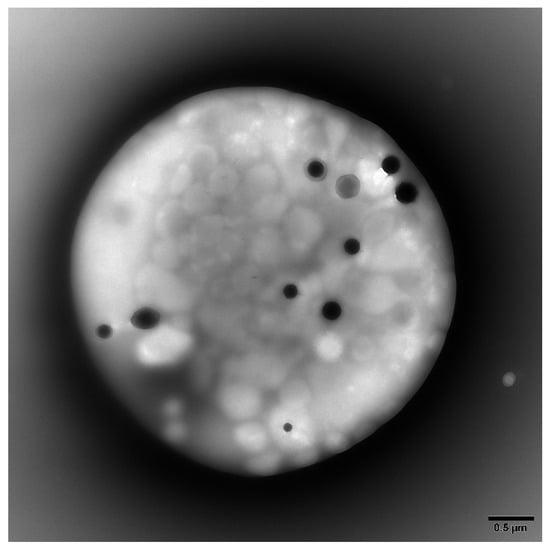

2.2. Platelet Preparations for Electron Microscopy

Platelet-rich plasma (PRP) was obtained from whole blood by centrifugation at room temperature for 15 min at 200 g. Electron microscopy coated copper grids used for platelet support were washed with deionized water following PRP incubation and air-dried. A FEI Tecnai G2 Spirit BioTwin transmission electron microscope (TEM, Hillsboro, OR) was used to determine the average number of DG/PL (Figure 1). Previous studies from this laboratory have established a normal value of 4.64 ± 0.11 (mean ± 1 SE DG/PL), consistent with the established literature [9,21,22].

Figure 1. Representative transmission electron microscopy image of a whole mounted and air-dried platelet. Dense granules appear as opaque round bodies (normal = 4–6/platelet; range 0–30/platelet), whereas the ill-defined gray bodies are alpha granules (50–80/platelet).